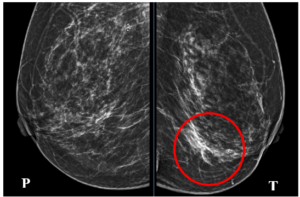

Ca lâm sàng: Chẩn đoán ung thư vú đồng thời 2 bên giai đoạn sớm tại Trung tâm Y học hạt nhân và Ung bướu – Bệnh viện Bạch Mai

Ca lâm sàng: Chẩn đoán ung thư vú đồng thời 2 bên giai đoạn sớm tại Trung tâm Y học hạt nhân và Ung bướu – Bệnh viện Bạch Mai GS.TS. Mai Trọng Khoa1,2, PGS.TS. Phạm Cẩm Phương1,2, ThS.BS. Phạm Minh Lanh1,2 BSNT Vũ Thị Thùy Linh1, 1Trường Đại...